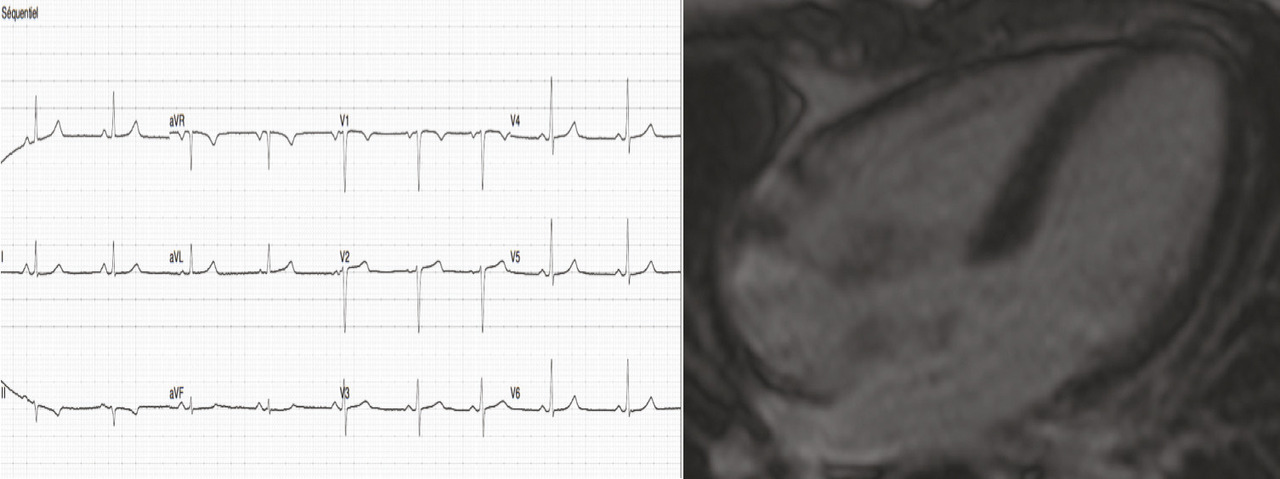

En juillet 2017, la patiente était revue en consultation de cardio- logie. Sa pression artérielle était mesurée à 100/68 mmHg, sa fréquence cardiaque à 54 batt/min, l’ECG s’était normalisé (fig. 3 ). Son traitement avait été majoré quelques semaines après sa sortie d’hospitalisation en cardio- logie, comprenant actuellement : bisoprolol 7,5 mg/j, ramipril 10 mg/j et spironolactone 25 mg/j.

La patiente était revue en consultation de cardiologie en septembre 2017 : sa pression artérielle était de 125/84 mmHg, sa fréquence cardiaque était mesurée à 86 batt/min, le BNP était à 35 ng/L, l’ECG était normal. L’échographie cardiaque montrait une FEVG à 52 % et un ventricule gauche non dilaté. L’IRM cardiaque montrait un ventricule gauche non dilaté, une FEVG à 56 %, sans réhaussement tardif ni séquelle d’infarctus. On maintenait le traitement par ramipril 10 mg et bisoprolol 7,5 mg. La spironolactone et le furosémide étaient arrêtés.

En juillet 2017, la patiente était revue en consultation de cardio- logie. Sa pression artérielle était mesurée à 100/68 mmHg, sa fréquence cardiaque à 54 batt/min, l’ECG s’était normalisé (